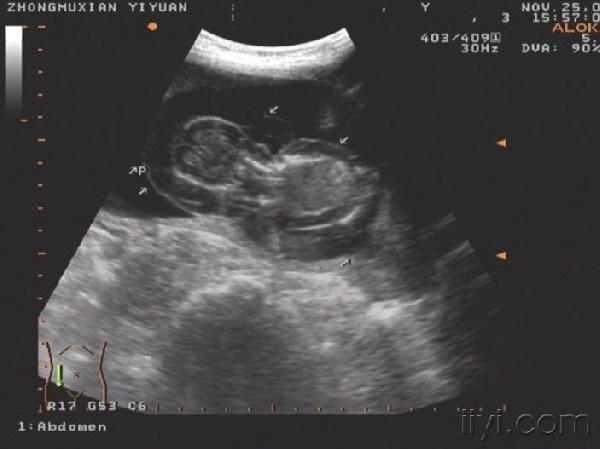

这个胎儿穿上了“太空衣”(典型胎儿水肿图片,值得分享!)

一位32岁经产妇,孕20周前来检查,发现胎儿被一层透明的膜状物包绕,从头颅到肢体,考虑胎儿水肿综合症!